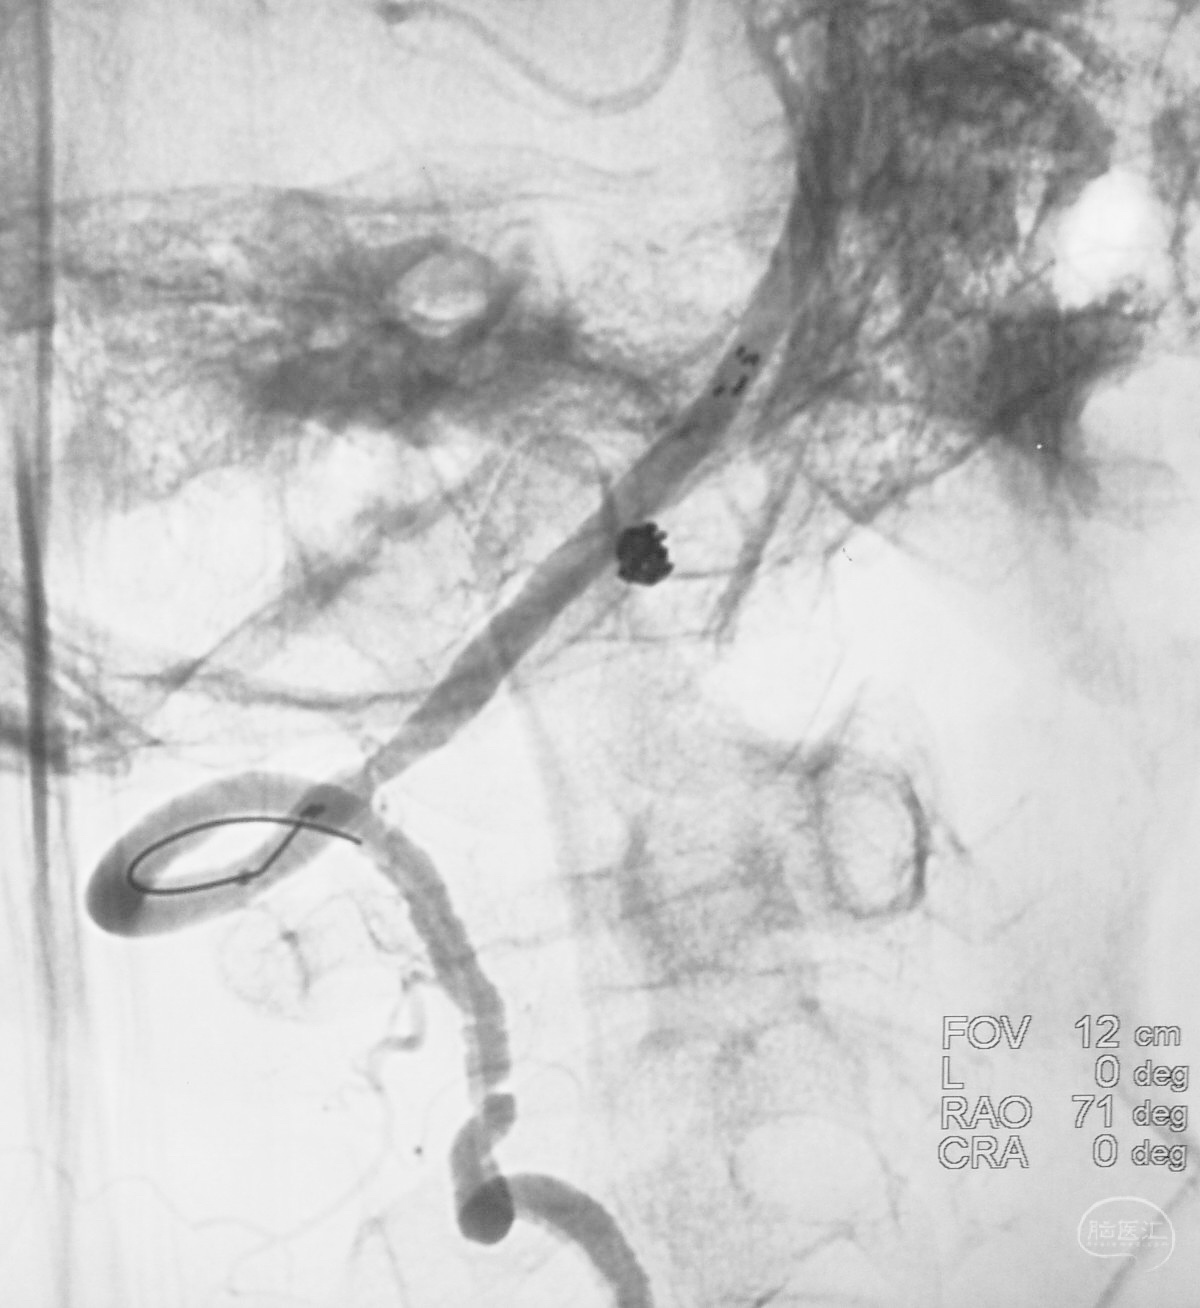

Echelon 10微导管头无论塑成C形还是S形,均无法稳定于动脉瘤腔内,遂使用回马枪技术,使微导管成襻通过,管头折返入瘤腔。

跨瘤颈释放Solitaire 4×20支架(蓝线),压住微导管(红线),在支架保护下经返折的微导管送入弹簧圈填塞瘤腔。

依次送入QC-2-4-3D,2-3-Helix,1.5-2-Helix,1.5-2-Helix四枚弹簧圈,最后一枚弹簧圈将管头(箭头)顶出瘤腔。

将Traxcess 14微导丝送入微导管,稍向远心端送微导管,使管头远离动脉瘤,再缓慢撤离。